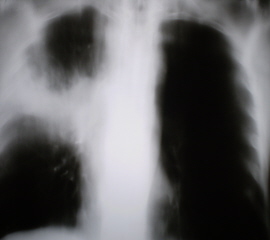

На рентгенограммах органов грудной полости, произведенных в стандартных проекциях – прямая и правая боковая (иллюстрации № 1 и № 2) определяется снижение прозрачности легочной ткани за счет инфильтрации в верхней доле правого лёгкого, с преимущественным поражением заднего и переднего сегментов. Также определяется снижение прозрачности легочной ткани в средней доле в виде очагов сливного характера с некоторым объёмным уменьшением. Плевра в главной и малой междолевых щелях плевра утолщена.